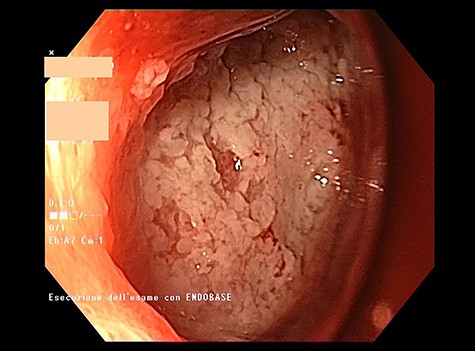

Intracavitary placement of E-VAC with prompt progressive improvement of the cavity size.

high PCR (291 mg/L) and the CT scan showed a right hydropneumothorax (Fig. 1). The first suspicion was an anastomotic leak and, in consideration of the hemodynamic instability and the severe septic state, the patient was submitted to emergency surgery. We performed a thoracoscopy with intraoperatively esophagogastroduodenoscopy which revealed a perforated prepyloric ulcer of the gastric tube. We therefore proceeded with accurate pleural toilette and closed the perforation with surgical stiches. At the end of the procedure, two thoracic drains and a naso-gastric tube with the distal end near the suture were placed. An additional naso-duodenum enteral feeding tube to ensure adequate nutrition was positioned. The patient was admitted in the Intensive Care Unit and supported with inotropic drugs, broad-spectrum antibiotics and proton pump inhibitor therapy. In the following days, the patient’s conditions improved allowing his extubation and his transfer to the surgical ward. Unfortunately, imaging and endoscopic check revealed a recurrent perforation. Considering the failure of the conservative approach, we decided to start the E-VAC Therapy on his 21st post-operative day (POD), using the Eso-SPONGE® System (B. Braun Surgical, S.A. Carretera De Terrassa, Rubi, Spain), firstly placed intraluminal because of the reduced size of the wall defect (Fig. 2). After three E-VAC replacements we did not observe any endoscopic or radiologic improvements. Moreover, on his 35th POD, due to a new impairment of vital signs, the patient underwent a second surgical treatment, with a new pleural toileting and another unsuccessful attempt of closing the conduit defect surgically. Considering the prolonged hospital stay, we placed a feeding jejunostomy. We proceeded with a new attempt of E-VAC, this time by placing it intracavitary (Fig. 3 and Fig. 4). The E-VAC was changed every 48–72 hours, reshaping the dimension of the sponge every time according to the size of the cavity. We observed a progressive reduction of the cavity size during the seriated endoscopic and CT evaluation. Considering the continuous improvement of patient’s clinical condition we discharged him after 84 days of hospitalization, with the E-VAC in place. The device replacement was carried on twice a week as an outpatient treatment, until its definitive removal (Fig. 5). The total duration of the therapy was 37 days with 13 E-VAC intracavitary interventions. Seven days after the device removal we performed an upper gastrointestinal X-Ray with oral contrast that showed no contrast medium leakage. The patient was therefore allowed to resume oral intake. At 6 months follow up the patient was in good clinical conditions; radiological test and endoscopy showed no abnormalities.